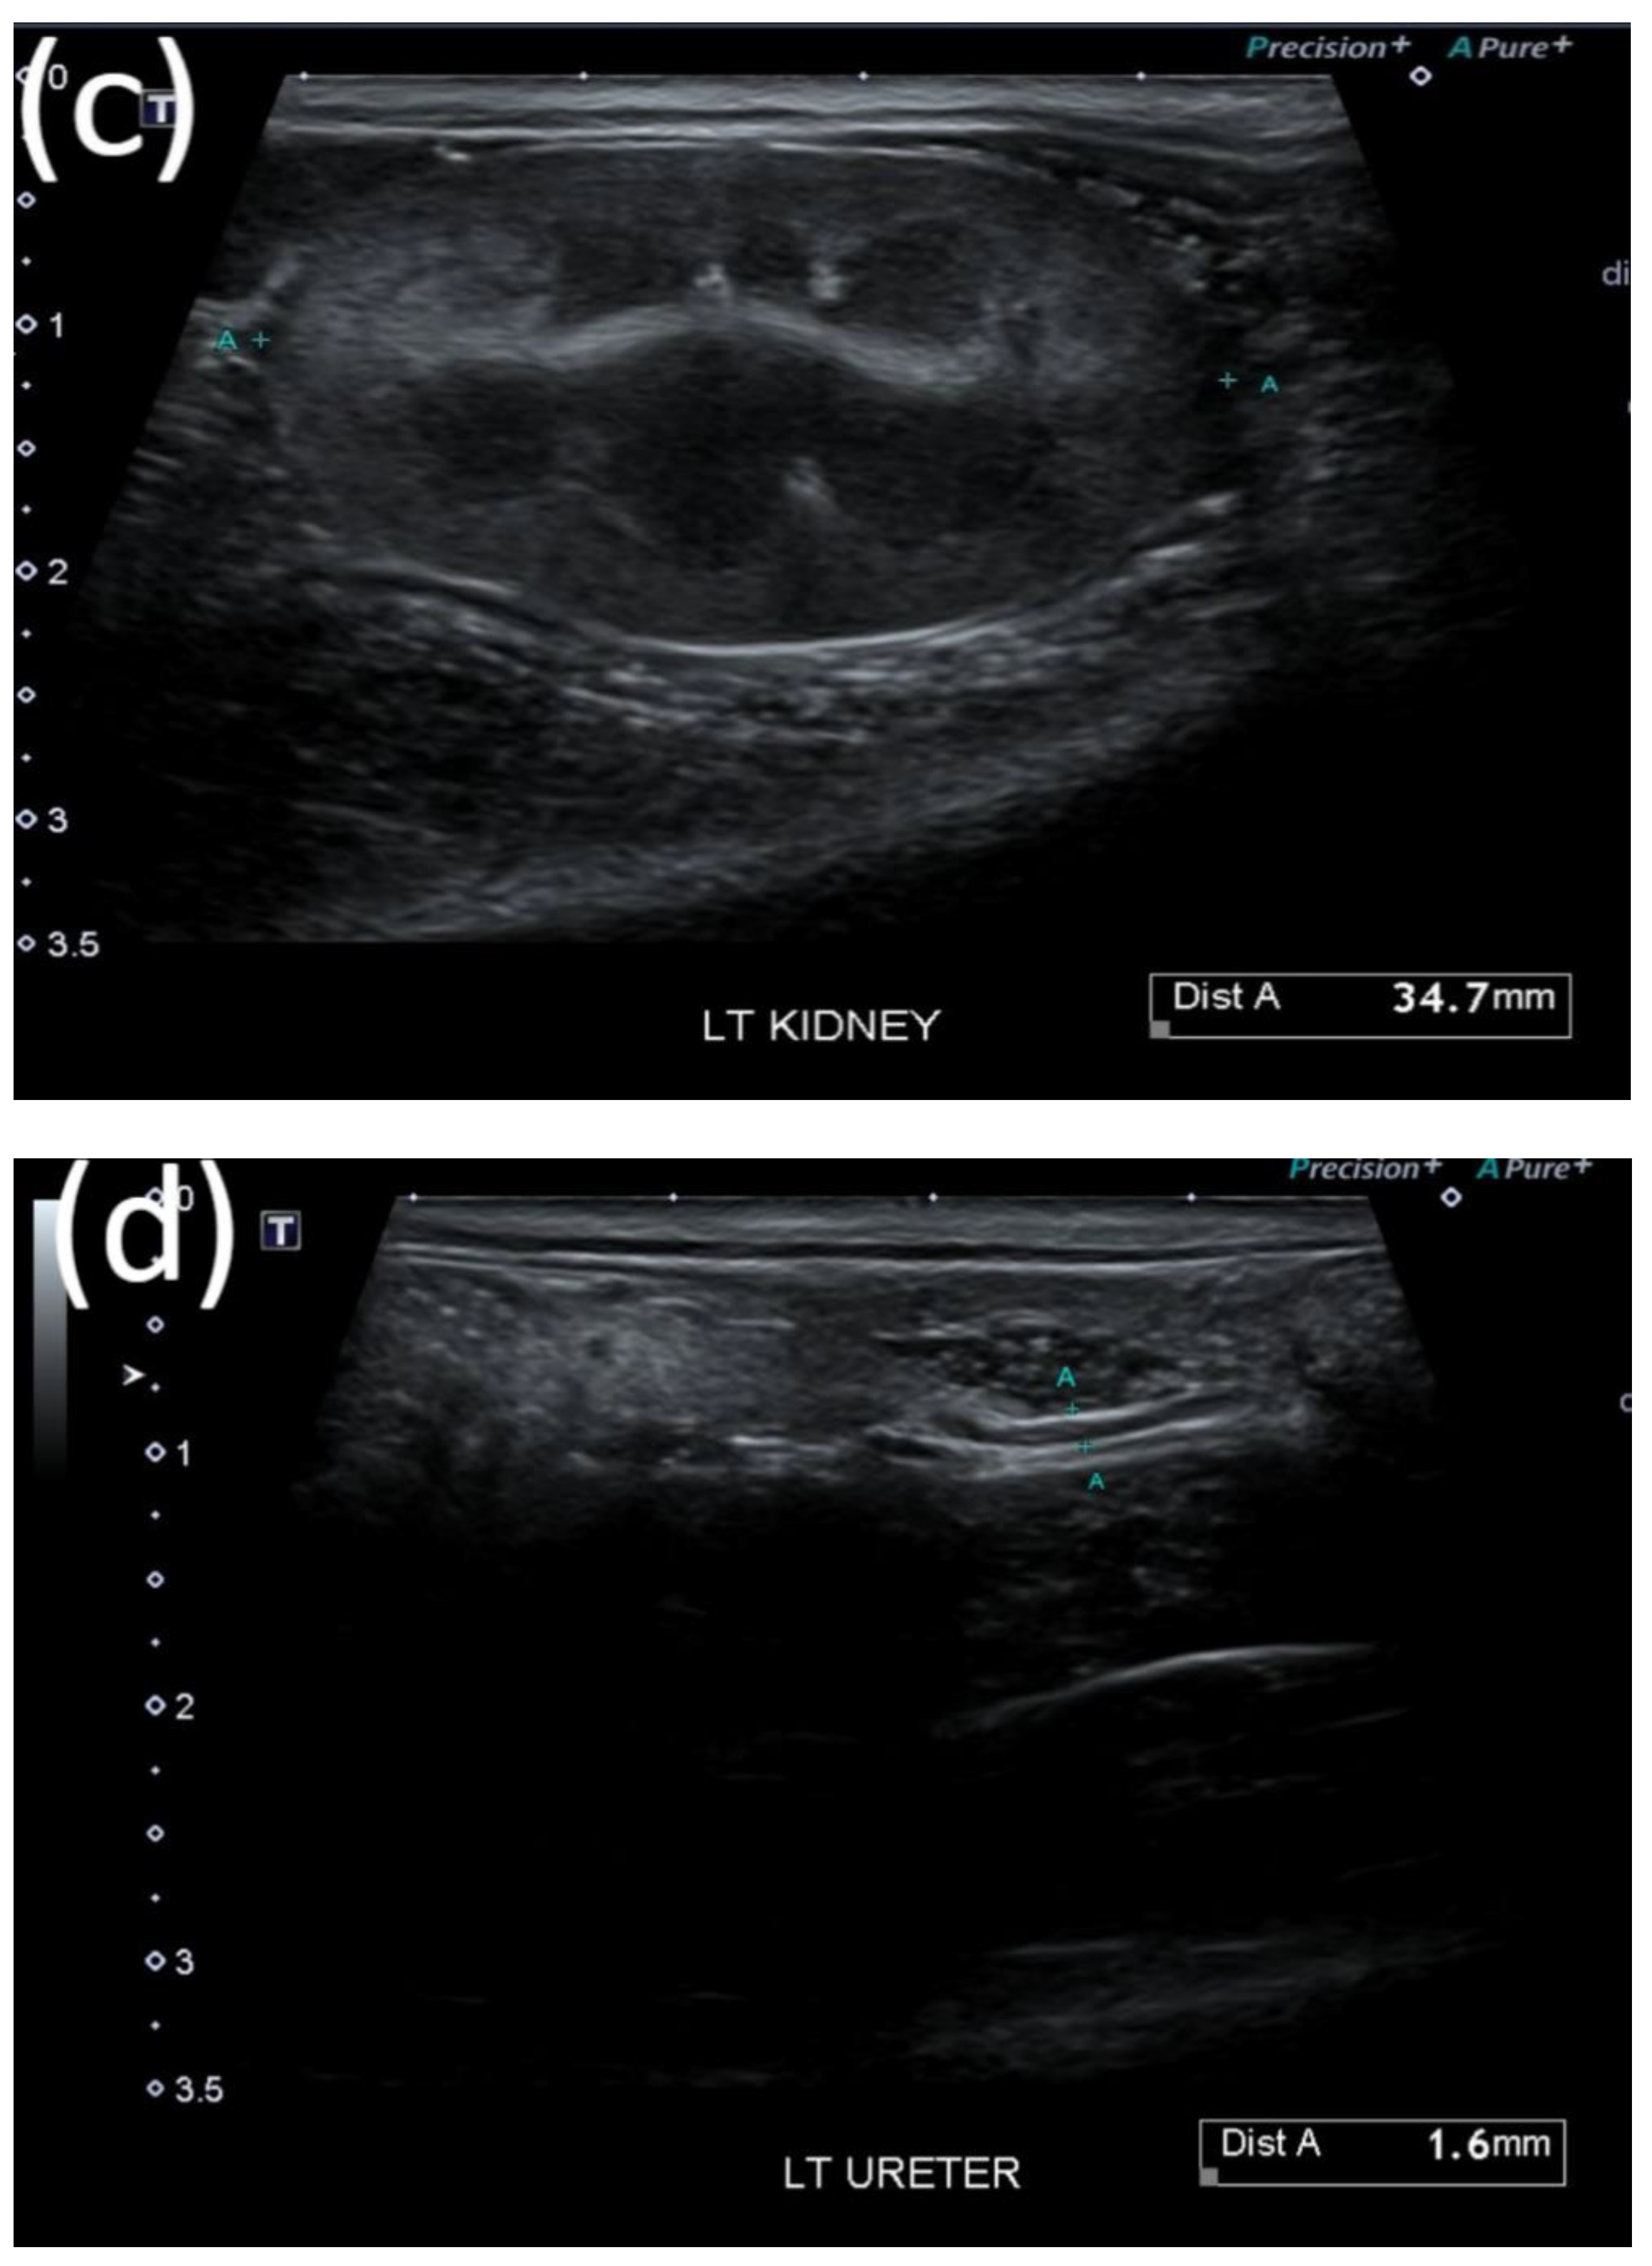

After surgical removal, the stone, which contained calcium oxalate, was confirmed to have a diameter of approximately 3 × 2 × 1 mm3. For cats in the stone passage success group, changes in the locations of the stones and improvement in the extent of renal pelvis dilatation owing to obstruction were observed on ultrasound (Figure 1a–d). In one case where bilateral ureteral stones resolved simultaneously, treatment was successfully terminated with a dramatic decrease in creatinine (Figure 2).

Figure 1.

Representative ultrasound image of successful stone passage in a cat. (a) Dilated renal pelvis owing to obstruction and (b) high-contrast material presumed to be a stone in the distal part of the ureter. (c,d) After tamsulosin therapy, improved renal pelvic dilation and successful stone passage were confirmed through ultrasound imaging.